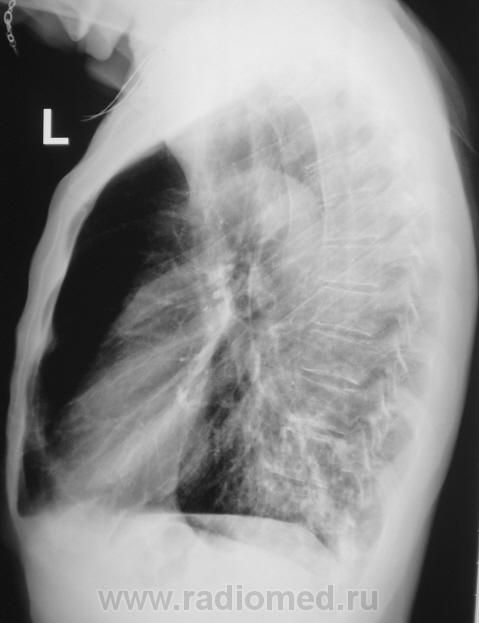

Пациент направлен на рентгенографию ОГК с диагнозом - "Левостороняя пневмония".

Анамнез стандартный. Ранее неоднократно страдал обострениями хронического бронхита. Сейчас вот не нашутку занемог - температура до 38, откашливает мокроту, кашель продуктивный.

Диагноз левосторонней нижнедолевой С10, С9 сементарной пневмонии наверное будет верным, а с учётом фона- с наличием бронхоэктазов.